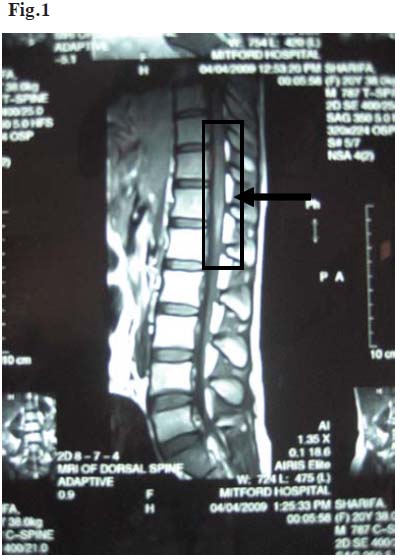

A 20 year-old young lady was admitted in Mitford Hospital in March 2009 with 10 days history of urinary retention, inability to defecate, gradual weakness of the lower limbs and fever. On query, she mentioned that the gradual weakness of her lower limbs was not progressive. The symptoms had started 5 days after receiving the third dose of chick embryo cell culture rabies vaccine. The vaccine was administered after she was bitten by a domestic cat one month ago. Her past medical history was unremarkable. On examination, her temperature was 99ºF and vital signs were stable. There was a bite mark on the lateral surface of her right forearm 2 cm from the lateral epicondyle. Neurological examination of the lower limbs revealed muscle power of 4/5, with increased reflexes and the planter reflexes were bilaterally extensor. Clonus was absent and her gait was normal. There was no sensory impairment. All deep reflexes of the upper limbs were exaggerated. The reminder of her neurological and physical examination was unremarkable. A full blood count revealed polymorphonuclear nutrophil leucocytosis and an erythrocyte sedimentation rate (ESR) of 20 mm in 1st hour. Other routine tests namely serum creatinine, random blood sugar, routine urine examination and X-ray of chest were normal. After excluding papilloedema by ophthalmoscopy lumbar puncture was done. Cerebrospinal fluid (CSF) was clear with lymphocyte pleocytosis (total white cell count 30 cells/mm3, lymphocyte 95%), glucose 4.2mmol/l (normal range: 3.3-4.4mmol/l) and protein 750mg/l (normal range:150-450 mg/l). Gram and Ziehl-Neelsen stains of CSF were negative. Serum VDRL test was non-reactive. A magnetic resonance imaging (MRI) of the spinal cord revealed swelling of the cord up to C6 to C7 disc level with isointense to high signal intensity on T1W1 images and high signal intensity on T2W1 images (Fig.1). MRI of the dorsolumbar spine was normal. The patient was diagnosed as post vaccination myelitis. A diagnosis of multiple sclerosis was considered but thought unlikely due to a definite history of recent vaccination and absence of optic neuritis and no relative afferent pupillary defect or any previous history.

Fig.1: MRI of the spinal cord showing swelling of the cord and high signal intensity at C6 to C7 level (arrow)